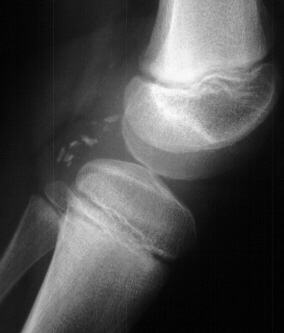

RADIOGRAPHS:

AP, lateral and obliques of the left knee showed an effusion with multiple radiodense bodies that were felt to be intraartictilar . No fractures or dislocations were evident. Comparison views of the right knee were unremarkable.